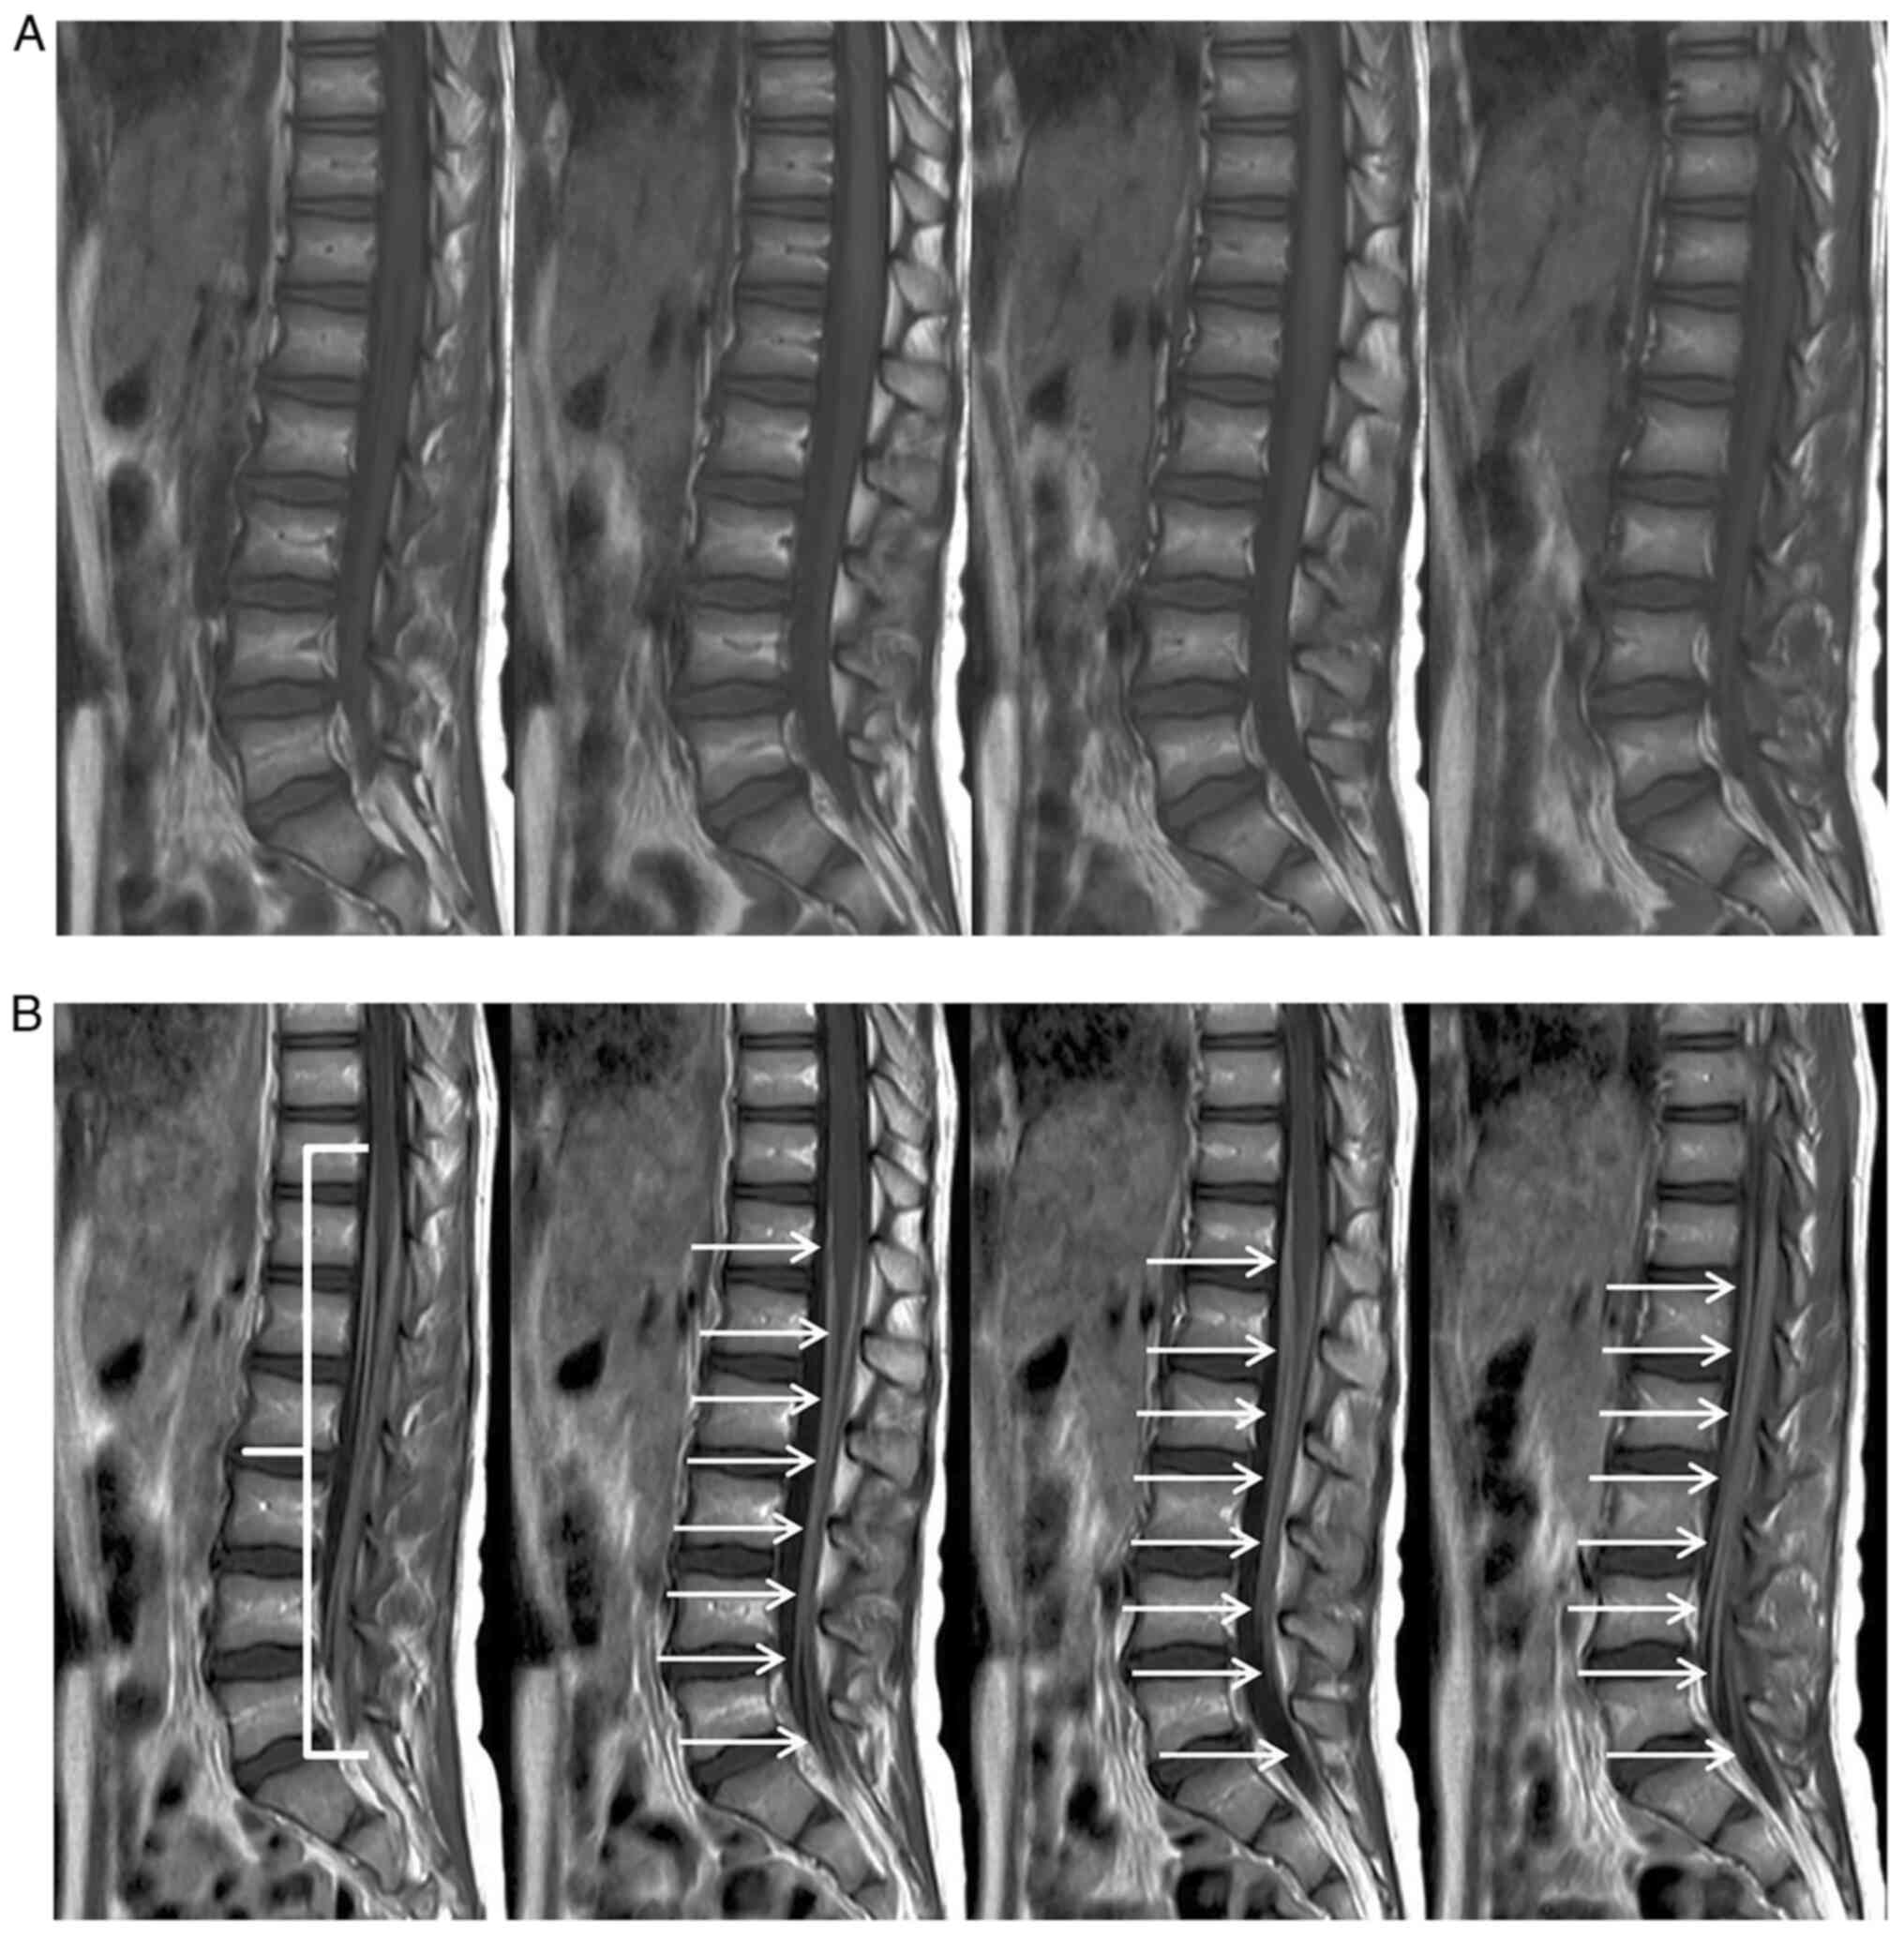

Cranial and spinal MRI (Philips Ingenia 1,5T; Spin-echo, Turbo Spin-Echo, Inversion Recovery, Gradient Echo, Echo Planar with T1, T2, DP weighted sequences, pre and post-contrast) showed marked enhancement of cauda equina roots after contrast injection, both in the sagittal (Fig. 1) and axial (Fig. 2) views, according to the clinical hypothesis of Guillain-Barré polyradiculonevritis.

Figure 1

Sagittal T1w turbo spin echo (A) pre- and (B) post-contrast magnetic resonance imaging. The marked contrast enhancement of cauda equina roots, suggestive of Guillain-Barré syndrome, is indicated by the arrows in (B).

Spinal MRI of our girl showed marked enhancement of cauda equina roots (Figs. 1 and 2).